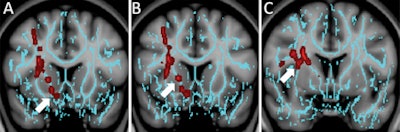

In the comparison with control subjects, DTI showed decreased fractional anisotropy in the superior longitudinal fasciculus, white matter around the nucleus accumbens, and anterior limb of the internal capsule in patients with mild traumatic brain injury and depression.

The concussed patients with anxiety had diminished fractional anisotropy in the vermis, compared with the controls. Interestingly, while irritability is a common symptom after concussion, the researchers found no regions of significantly decreased fractional anisotropy in the concussed patients with irritability.

Another notable finding was that injury in the nucleus accumbens region was associated with recovery time in the concussed patients with depression. The nucleus accumbens essentially serves as the brain's reward center and is often abnormal in patients with a major depressive disorder.